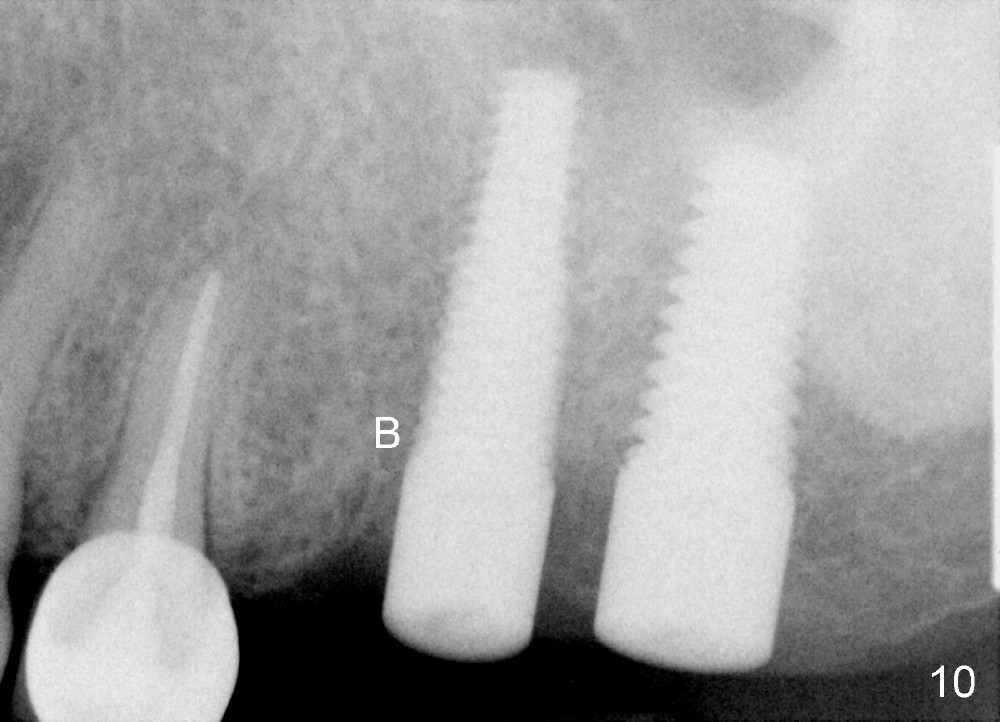

Three months and a half postop, there is bone growth in the previous mesiobuccal socket (Fig.10 (B), compare Fig.5,7). Soft tissue also heals (Fig.11). Using a larger implant (7 mm in diameter) may facilitate wound healing (Fig.12, as compared to Fig.2).